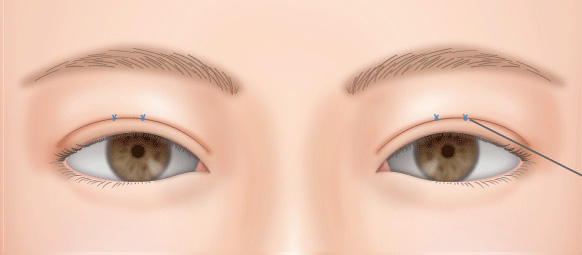

施術の前には、実際に鏡などで患者様に確認いただきながら、シミュレーションを行い、自然で似合ったデザインを行います。ドクターの指名がございましたらご遠慮なく予約時にご希望ください。

二重の幅が広くなり過ぎて、いかにも整形っぽい目になることがあります。

切開法の場合、前回の手術の切開線の傷跡の上(眉毛側)で新たに作る二重のラインに沿って切開し、幅を広げ、自然な形にすることができます。

二重の幅が思ったより狭かった場合もあります。

切開法の場合、もう一度切開手術をすれば、可能な限り広げられます。

蒙古ひだが強く張っている場合は、目頭切開をすると平行型になる場合があります。

埋没法でもう一度二重の幅を広げれば平行型になることもありますが、ミニ切開法や全切開法をご提案する場合もあります。